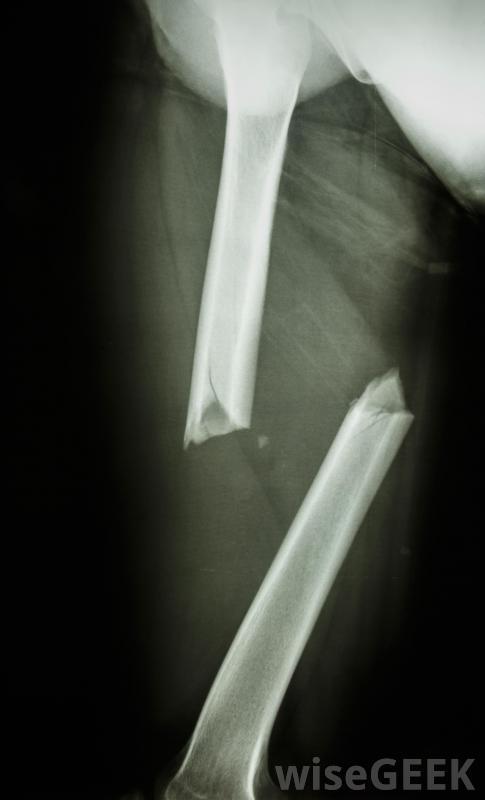

用于修复严重骨折的杆可以是骨整合的骨整合的一个明显的用途是安装牙科植入物这种植入物可以与颌骨结合在一起,使牙医能够在植入物上安装一颗牙齿。美容牙科学和重建牙科学都可以利用这种植入技术。这个过程也可以用来为假肢、鼻子等假肢制造锚固件,和耳朵。假肢可以用骨整合锚栓更加稳定和安全地连接,提高患者的舒适性和功能性。

用于修复严重骨折的杆可以进行骨整合用于修复严重骨折的杆也可以进行骨整合在这些过程中,杆在骨愈合的同时使其保持稳定,同时还增加了支撑和结构,以保护骨骼在将来不会再次断裂。通过对该部位进行x光和医学影像学研究,可以判断骨愈合的进展,以确认骨在植入物中生长,并且骨生长均匀